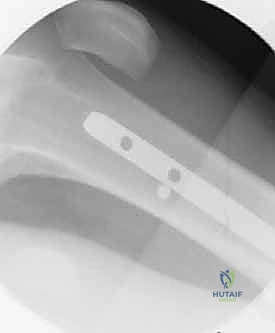

6. القفل (Interlocking)

يتم إدخال مسامير قفل عبر المسمار النخاعي من الأعلى (بالقرب من الورك) ومن الأسفل (بالقرب من الركبة) باستخدام أجهزة توجيه دقيقة لضمان عدم تحرك الكسر.